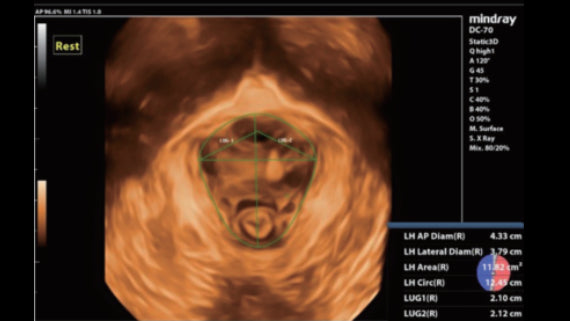

El Ultrasonido premiumDC-70 X-Insight de Mindray es un equipo de última tecnología para ecografías. Ofrece excelente resolución y sensibilidad para una visualización clara y precisa de los tejidos bajo examen. Esta máquina de alto rendimiento ofrece eficiencia y fiabilidad para una mayor precisión diagnóstica.